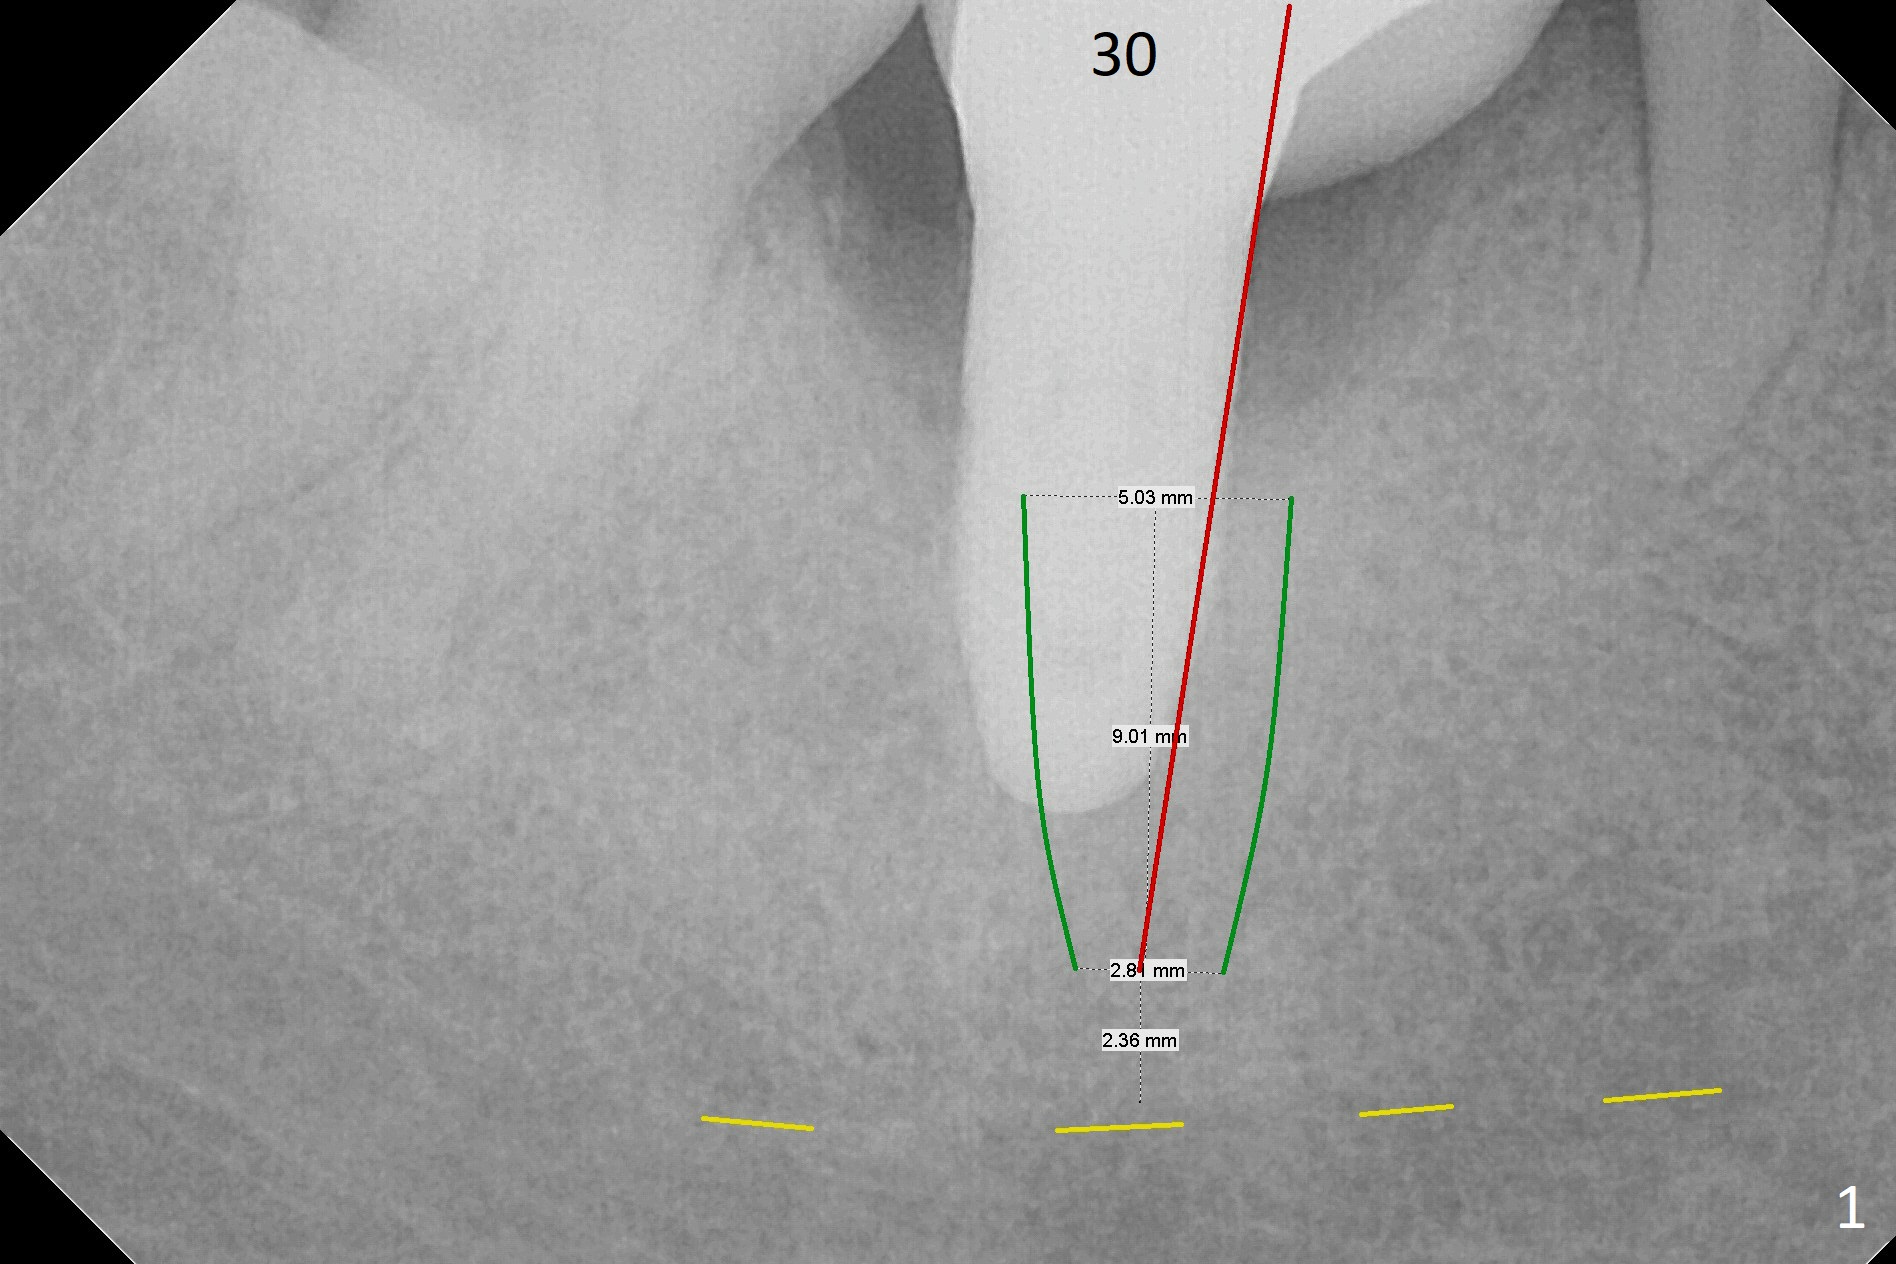

A 53-year-old woman has buccal gingival erythema and edema with deep pocket and purulent discharge. PA and CBCT show that the implant was placed distal and not deep enough (Fig.1,2) as well as buccal (Fig.3). When the failed implant is removed, try to place an implant mesiolinguoapically. Make purchase point/trough mesiolingual to the failed implant. Take PA with pilot drill for trajectory confirmation (Fig.1 red line). The implant will be 4 or 4.5 mm in diameter and 4 mm in the native apical bone. Use 1.6 and 3.8x11 mm Magic Drill until the lingual crest. Place PRF over the bone graft, Cyotplast buccally and provisional. Lower Molar Immediate Implant, Prevent Molar Periimplantitis (Protocols, Table), Armaments, #19 Xin Wei, DDS, PhD, MS 1st edition 12/10/2017, last revision 09/15/2020